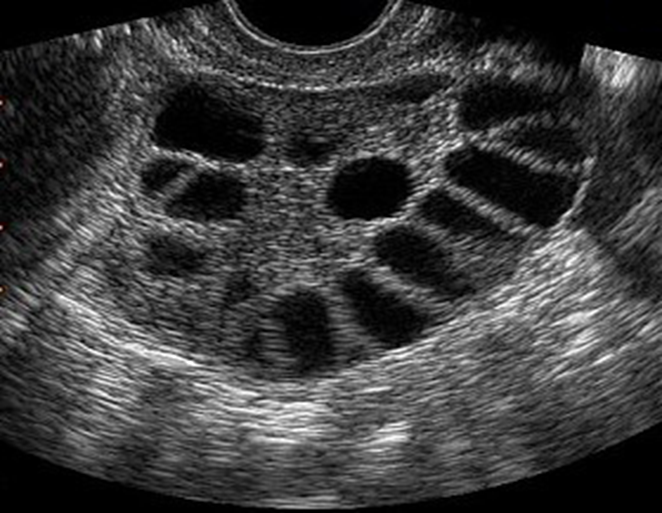

There should be 10 or more cyst, enlarge ovaries. These patients present with hirsutism, obesity, infertility, irregular menstruation and acne etc.

typical features of polycystic ovaries on ultrasound or MRI

include large volume ovaries with multiple small follicles arranged around the periphery, forming the appearance of a ‘string of pearls’

Transvaginal ultrasound of the right and left ovary:

both ovaries contain multiple anechoic, subcapsular cysts with a “string of pearls” appearance and posterior acoustic enhancement. There is a relative increase of stromal tissue and capsule thickness with increased ovarian size.